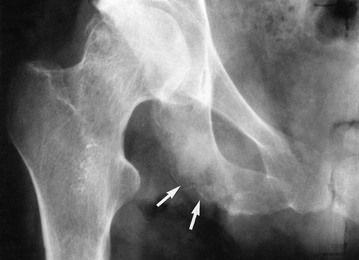

• Injuries resulting from falls from trolleys or from the operating table during positioning

• Injury to diseased bones and joints from manipulation or positioning. These include dislocation of rheumatoid atlanto-axial joints and dislocation of a prosthetic hip joint